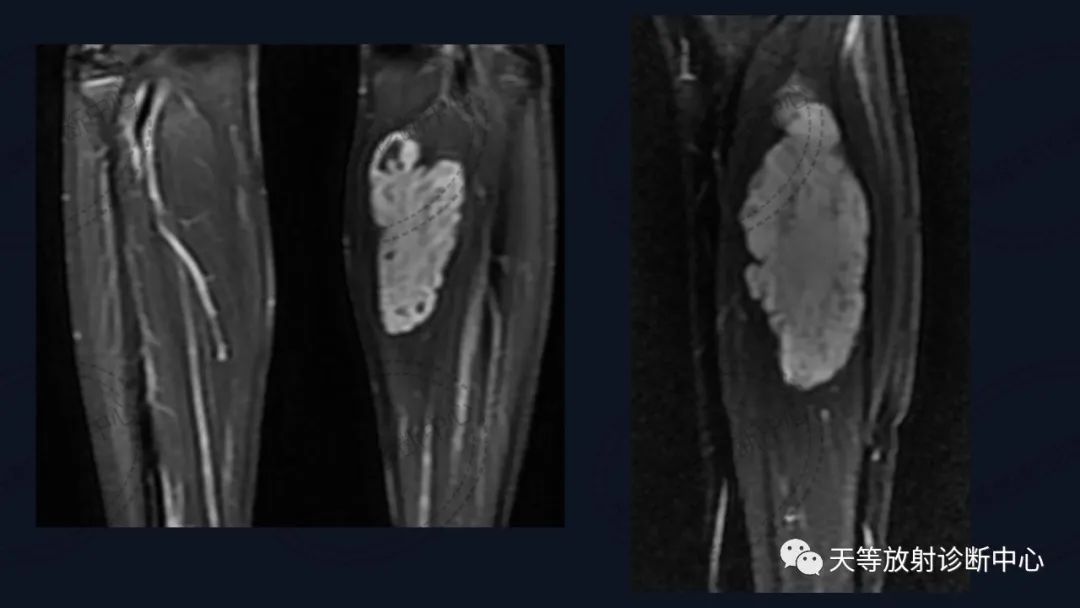

病例,儿童男性

上图:压脂序列肿块椭圆形,内部见细小分隔,血管流空信号。

前后两次对比观察,病灶略有增大。

组织学上主要表现为血管管道数目的增加及纤维结缔组织、平滑肌、炎性细胞和毛细血管、淋巴管等不同程度的浸润。MRI观察病灶内纤维结缔组织呈分隔状及线状低信号影,含血管成分可表现血管流空信号影。病灶内出血表现信号混杂等。